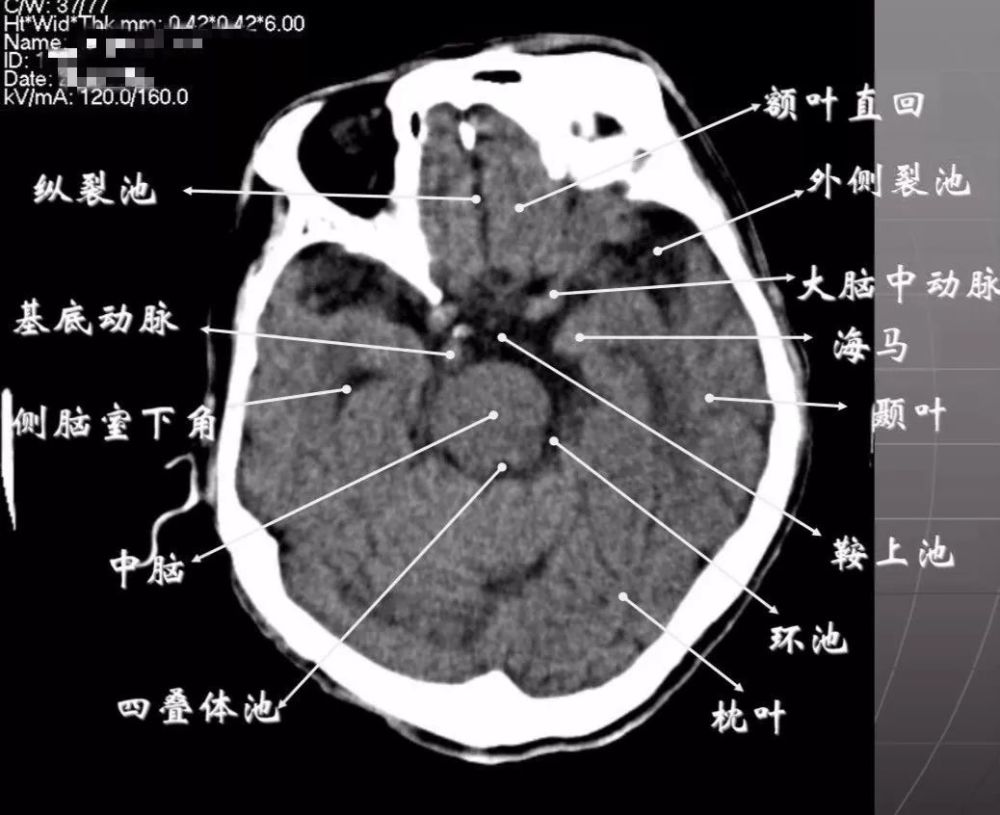

脑积水ct图解

头颅ct影像解剖ppt

颅脑ct诊断ppt

读懂头颅ct并不难,教你成为读片小能手

ct片的阅读技巧(头部)

头颅ct基本知识与常见疾病

简明又详细的头部ct读片详解,收藏!_腾讯新闻

分类:医学图片 颅脑ct,mri基本读片知识 轴位: